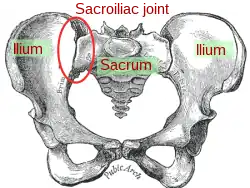

Human female pelvis, anterior view, with sacroiliac joint within red ellipse. | |

The sacroiliac joint or SI joint (SIJ) is the joint between the sacrum and the ilium bones of the pelvis, which are connected by strong ligaments. In humans, the sacrum supports the spine and is supported in turn by an ilium on each side. The joint is strong, supporting the entire weight of the upper body. It is a synovial plane joint with irregular elevations and depressions that produce interlocking of the two bones.[1] The human body has two sacroiliac joints, one on the left and one on the right, that often match each other but are highly variable from person to person.[1]

Sacroiliac joints are paired C-shaped or L-shaped joints capable of a small amount of movement[2] (2–18 degrees, which is debatable at this time) that are formed between the auricular surfaces of the sacrum and the ilium bones. However most[3] agree that there are only slight movements occur on these joints, with only 3 degrees range of motion during flexion-extension, followed by 1.5 degrees axial rotation, and 0.8 degrees lateral bending.[4] The joints are covered by two different kinds of cartilage; the sacral surface has hyaline cartilage and the iliac surface has fibrocartilage.[2] The SIJ's stability is maintained mainly through a combination of only some bony structure and very strong intrinsic and extrinsic ligaments.[5] The joint space is usually 0.5 to 4 mm.[6]

Aging changes the characteristics of the sacroiliac joint.[7] The joint's surfaces are flat or planar in early life. Once walking ability is developed, the sacroiliac joint surfaces begin to develop distinct angular orientations and lose their planar or flat topography.[2] They also develop an elevated ridge along the iliac surface and a depression along the sacral surface.[8] The ridge and corresponding depression, along with the very strong ligaments, increase the sacroiliac joints' stability and makes dislocations very rare. The fossae lumbales laterales ("dimples of Venus") correspond to the superficial topography of the sacroiliac joints.